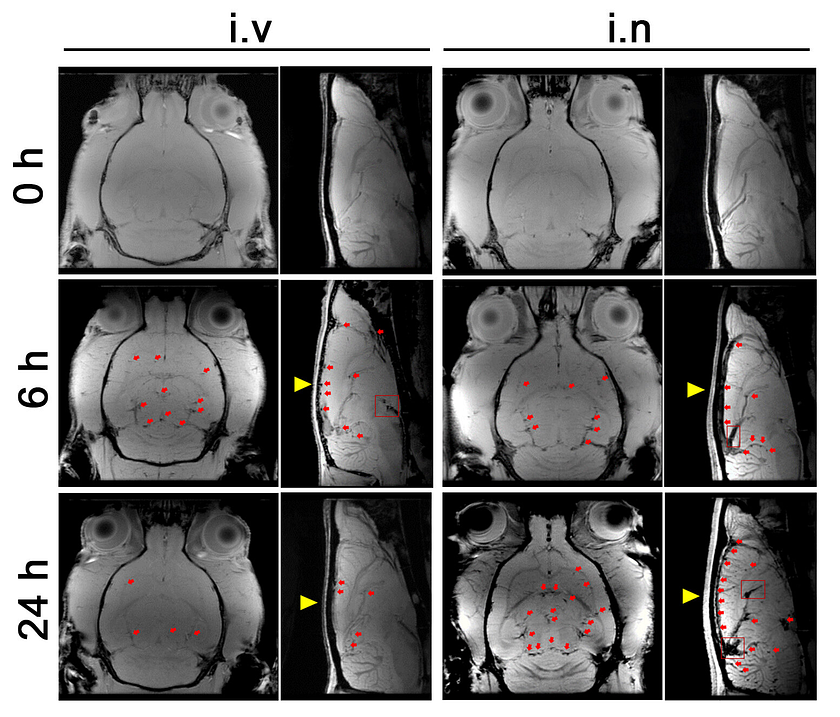

MRI view of rat brains after delivery of nanoparticles: The dark spots pointed to by red arrows and circled by red boxes indicate nanoparticles. The yellow arrow shows the location of the permanent magnet placed on the skull to attract the nanoparticles. (I.v., intravenous administration. i.n., intranasal administration. Sample size for imaging is 5 male rats.). Credit: Dr Gang Ruan, Xi’an Jiaotong-Liverpool University